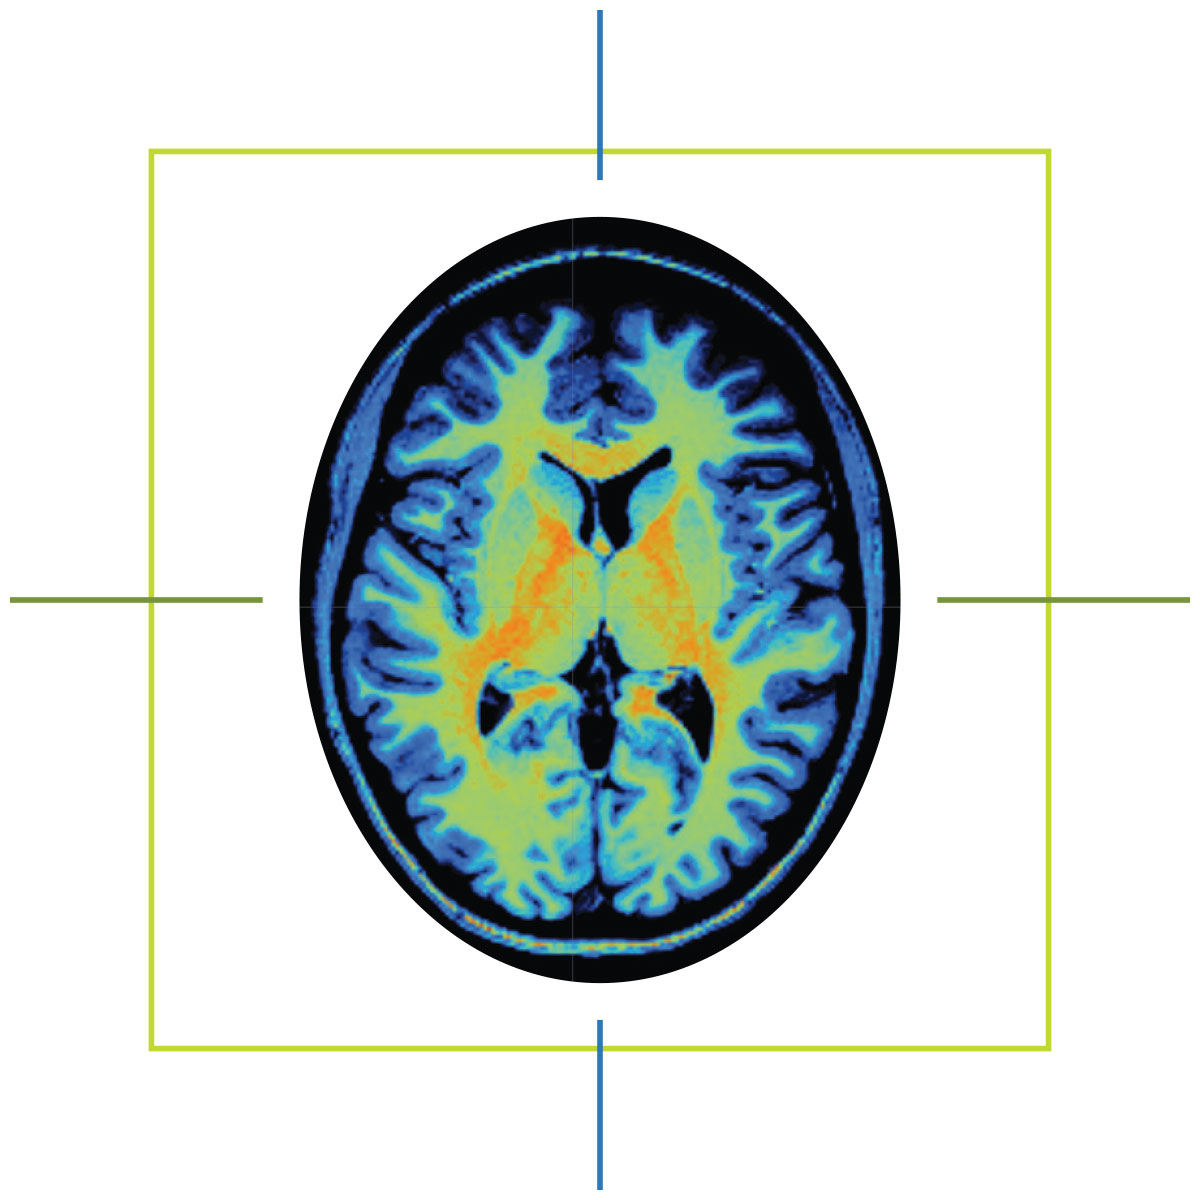

When Marcus Ryninger tells people how his life changed on May 1, 2015, he shows them an MRI scan saved to his phone.

He also knew his speech would never return to how it was before the stroke. But after seeing the scan of his brain — the dark hole of necrotic tissue on one side, the vibrant patchwork of healthy tissue on the other — the man who spent 30 years as a mechanic and quality control supervisor in the Navy understood: The stroke had not taken his determination.

Before hospitals began using magnetic resonance imaging machines, or MRIs, for clinical use in the 1980s, physicians had a limited window inside the human body. X-rays could capture images of a patient’s bones. CT scans could even see soft tissues like muscles and organs. But both imaging methods exposed patients to ionizing radiation, and both were poorly suited to distinguish soft tissue variations critical for identifying ligament issues, brain anomalies and some types of tumors.